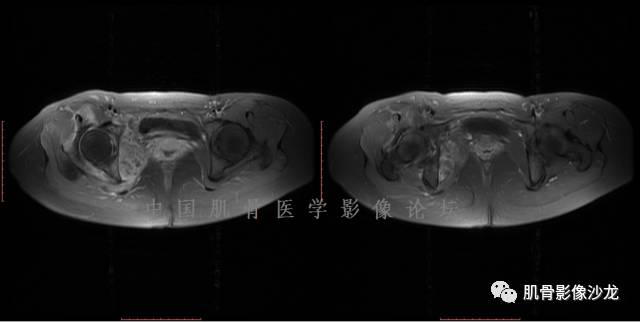

患者于2月前无明显诱因下出现腰骶部疼痛,夜间为重,逐渐加重伴左下肢麻木、疼痛,并有行走活动受限,在我院就诊,摄腰椎及骶髂部CT提示:腰椎骨质退变,腰3-4、4-5椎间盘膨出,骶髂关节炎。自用非甾体抗炎药无好转,再次来院就诊,门诊拟“骶髂关节炎”收住我科。病程无间歇性跛行,大小便正常。

专科检查:神清,脊柱无侧弯后凸畸形,椎体各节段无压、叩痛,双侧棘突旁无压痛,双侧骶髂关节压痛明显,左下肢放射痛,浅感觉较健侧减退,腰椎前屈后伸活动受限,膝、跟腱反射正常。

辅助检查:腰椎及骶髂部CT提示:腰椎骨质退变,腰3-4、4-5椎间盘膨出,骶髂关节炎。

雪舞 :第二例,位于骶骨,有骨质破坏并有软组织肿块,软组织肿块边界清

向以四 : 病例2 感染性骶髂关节炎 TB可能大,左侧梨状肌受累、肿胀增粗,并见低密度脓肿?

西门吹雪:考虑恶性肿瘤 的确有些难

晴朗 :倾向肉瘤

医影在线 : 转移瘤要除外

致远 : 或者软骨肉瘤

张小林:炎性病变和肿瘤的鉴别

飞鹰行动 :有一定的骨质硬化,骨肉瘤及软骨肉瘤可能性大 晴朗: 有骨膜反应,有软组织肿块

雪舞: 第二例我们能够看到破坏与软组织肿块不成比例,软组织肿块大,破坏小

医影在线: 病变无明显钙化

雪舞 :第二例挺难的,骨质破坏是溶骨性的,局部皮质中断,软组织肿块外缘光滑